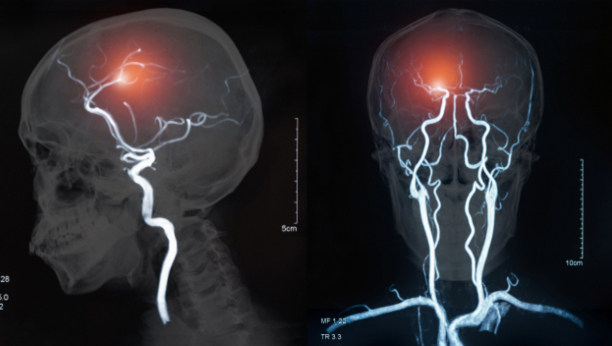

Bila je voljna da pokuša nešto ekstremno: ugraditi elektrode u njen mozak kao deo eksperimentalne terapije. Istraživači kažu da bi tretman - duboka moždana stimulacija ili DBS - mogao na kraju pomoći milionima u depresiji koja se opire drugim tretmanima.

Tretman daje pacijentima ciljane električne impulse, slično kao pejsmejker, ali za mozak. Sve veći broj istraživanja obećava, dok je par njih još uvek u toku, uprkos tome što su dve velike studije koje nisu pokazale prednost upotrebe DBS-a za depresiju privremeno zaustavile napredak.